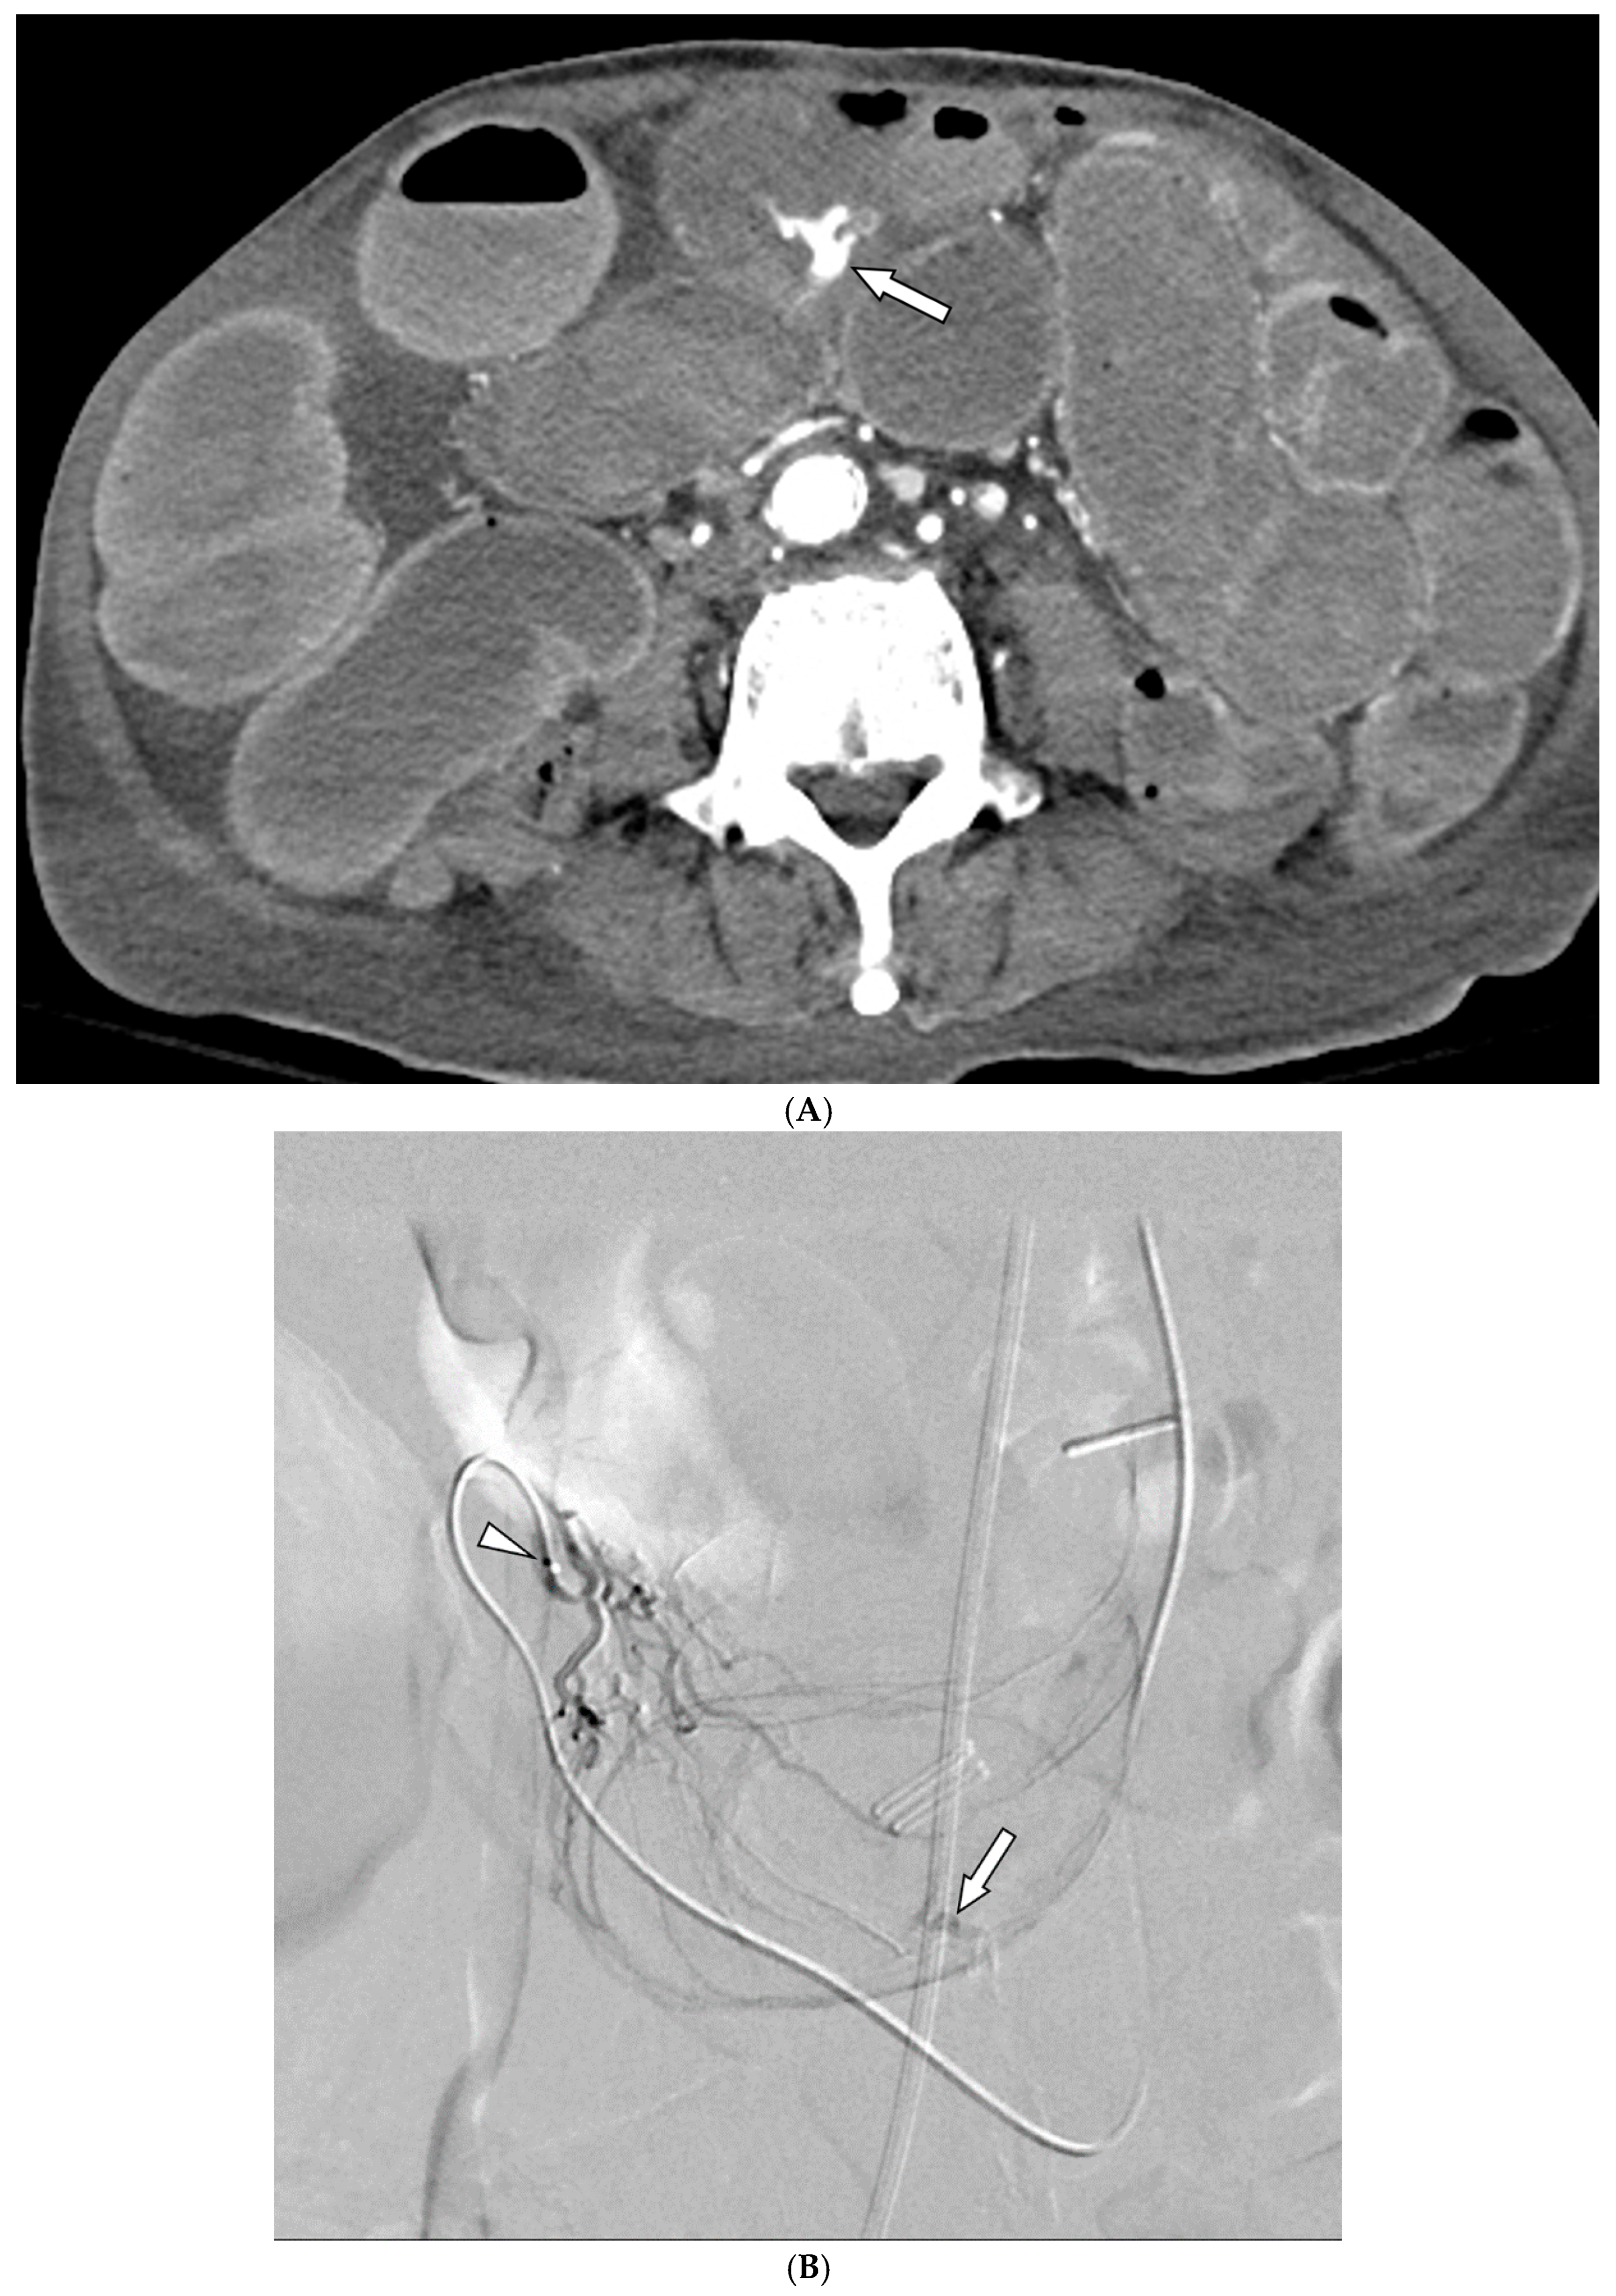

- Alali, M.; Cao, C.; Shin, J.H.; Jeon, G.; Zeng, C.H.; Park, J.-H.; Aljerdah, S.; Aljohani, S. Preliminary report on embolization with quick-soluble gelatin sponge particles for angiographically negative acute gastrointestinal bleeding. Sci. Rep. 2024, 14, 6438. [Google Scholar] [CrossRef]